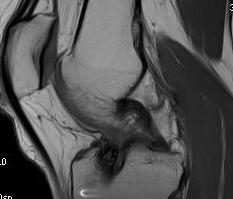

Coronal MRI can see ACL stump remnant, graft not intact. First sagittal confirms tunnel lysis.

Second demonstrates that femoral tunnel is sufficiently posterior